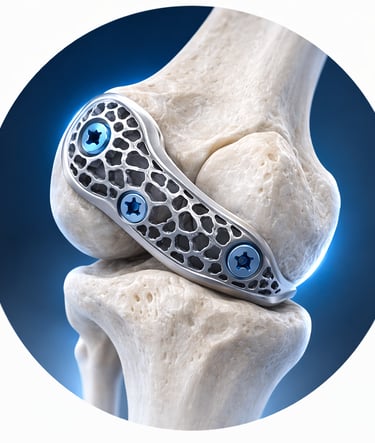

Custom-designed implants developed using advanced planning and manufacturing techniques

PATIENT-SPECIFIC IMPLANTS